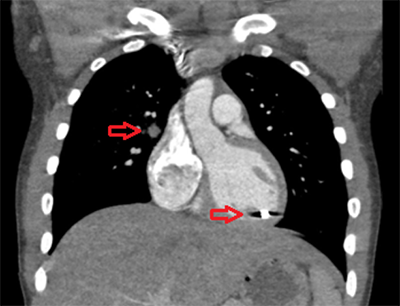

A chest radiograph (Figure 1) was obtained which showed a foreign body overlying the left hemithorax at the level of the apex of the cardiac silhouette.

Figure 1. Arrows pointing to entrance wound marked with a clip and foreign body inside the cardiac silhouette.